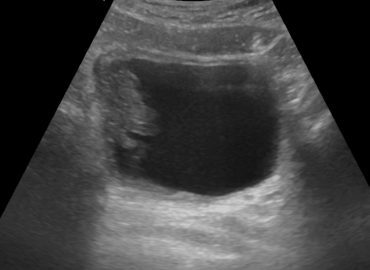

Paciente masculino de 30 años de edad, con dolor abdominal y hematuria.